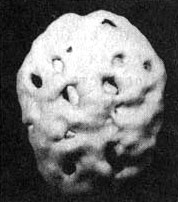

На иллюстрации — мозг сорокадевятилетнего пациента, который вдыхал пары токсических веществ на протяжении 12 лет. По своему виду этот мозг сильно напоминает мозг, пораженный кокаином или метамфетамином.

Мозг токсикомана

Трехмерное изображение поверхности, вид сверху. Обратите внимание на обширные «провалы» активности на всей поверхности мозга.